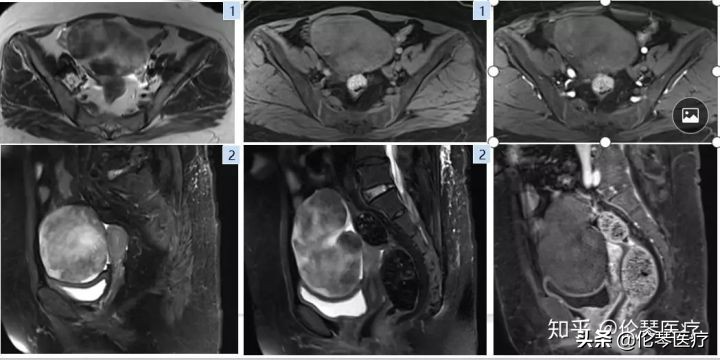

如图所示是卵巢肿瘤中另一种比较常见的实性肿瘤——卵泡膜纤维瘤,在绝经后妇女中发病率比较高。卵泡膜纤维瘤是一种良性肿瘤,如果术前能够很清楚地诊断出来,对患者的预后和心理都非常有帮助。磁共振在这方面,非常有价值。卵泡膜纤维瘤里含有大量纤维组织,这些纤维组织在CT和超声上,都没有特异性,分辨不出来,但在磁共振上,T2WI表现为低信号,非常有特征性,很容易就能得出诊断。

磁共振的另一优势在于多方位成像,成像范围大(大FOV),这也是基于卵巢肿瘤本身具有的特点。因为卵巢肿瘤通常会长很大,占据整个腹部,超声对于这么大的肿瘤,很难了解到细节。而磁共振多方位成像就可以全面了解肿瘤的上下左右关系,以及肿瘤和血管之间的关系。